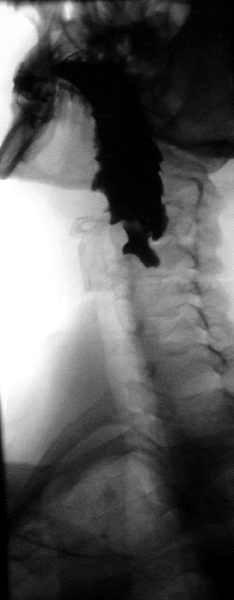

바륨 연하 검사는 '''바륨 식도 조영술'''이라고도 하며, 단독으로 후두, 인두 및 식도를 검사할 때는 거의 준비가 필요하지 않다.[10][11]

바륨 연하 검사는 식도 위 십이지장 내시경 검사 결과가 음성임에도 지속되는 연하 곤란 및 연하통, 내시경 검사 실패, 식도 운동 장애, 구인두 이물감, 기관식도루 평가, 식도 이완 불능증 치료 경과를 모니터링하기 위한 시간별 바륨 연하 검사 등에 사용된다.[12] 황산 바륨 현탁액은 100ml 이상, 농도 200~250%의 E-Z HD, 100% Baritop과 같은 것을 사용할 수 있다. 식도 천공이 의심되는 경우 바륨 대신 Gastrografin (디아트리조산) 및 Conray (이오탈람산)과 같은 수용성 조영제를 사용한다. 폐 흡인의 위험이 있거나 기관식도루가 있는 경우 가스트로그래핀 대신 농도가 300 mg/ml인 저 삼투압 조영제를 사용한다.[12]

두꺼운 바륨 혼합물을 앙와위 자세에서 삼키고, 삼키는 과정을 투시 영상으로 촬영한다. 그런 다음 얇은 바륨 혼합물을 여러 번 삼키고, 투시 및 표준 방사선 촬영으로 통과 과정을 기록한다. 검사 테이블을 다양한 각도로 기울여 이 절차를 여러 번 반복한다. 이 과정에서 총 350–450 mL의 바륨을 삼킨다.[13][14] 일반적으로 15초 후에 섭취한 액체의 90%가 위로 통과해야 한다.[15]

오른쪽 앞쪽 사위(RAO) 시야는 겹치는 척추에서 벗어나 식도를 명확하게 볼 수 있게 한다.[12] AP(전후) 시야는 위식도 접합부를 시각화하기 위해 사용된다.[12] 초당 3~4프레임 속도로 삼키는 동안 하인두를 시각화하기 위해 AP 및 측면 시야도 촬영한다. 왼쪽 뒤쪽 사위(LPO) 자세는 탈장, 점막 링 및 정맥류를 식별하는 데 사용된다.[12]

바륨 연하 검사(바륨 식도 조영술)는 후두, 인두 및 식도를 검사하며, 검사 전 특별한 준비가 필요하지 않을 수 있다.[10][11] 그러나 소장 추적 검사의 경우, 검사 전에 6시간 동안 금식해야 한다.[16] 장액 주입술(소장 관장)의 경우, 8시간 금식 외에도 장 준비와 세척을 위해 변비약이 필요할 수 있다.[11]

바륨 연하 검사 시, 두꺼운 바륨 혼합물을 앙와위 자세에서 삼키고, 삼키는 과정을 투시 영상으로 촬영한다. 그 후 얇은 바륨 혼합물을 여러 번 삼키고, 투시 및 표준 방사선 촬영으로 통과 과정을 기록한다. 검사 테이블을 다양한 각도로 기울여 이 절차를 여러 번 반복하며, 총 350–450 mL의 바륨을 삼킨다.[13][14]

- 연하곤란: 바륨 연하 검사는 위내시경보다 식도 웹과 링을 감지하는 데 더 민감하며,[3] 구강인두 연하곤란의 초기 평가에 유용하다.[25] 또한, 내시경으로 보기 어려운 인두 종양을 발견할 수 있다.[27] 젠커 게실은 바륨 연하 검사에서 관찰되는 대표적인 질환 중 하나이다.